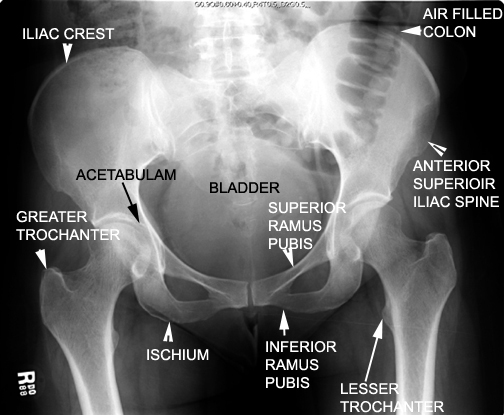

Identify the pelvic bones and joints. Click the image for labeling.